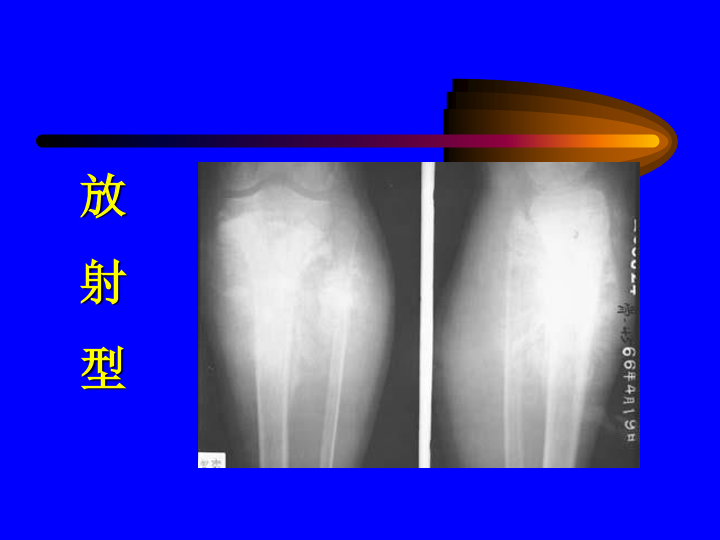

骨和关节X线诊断